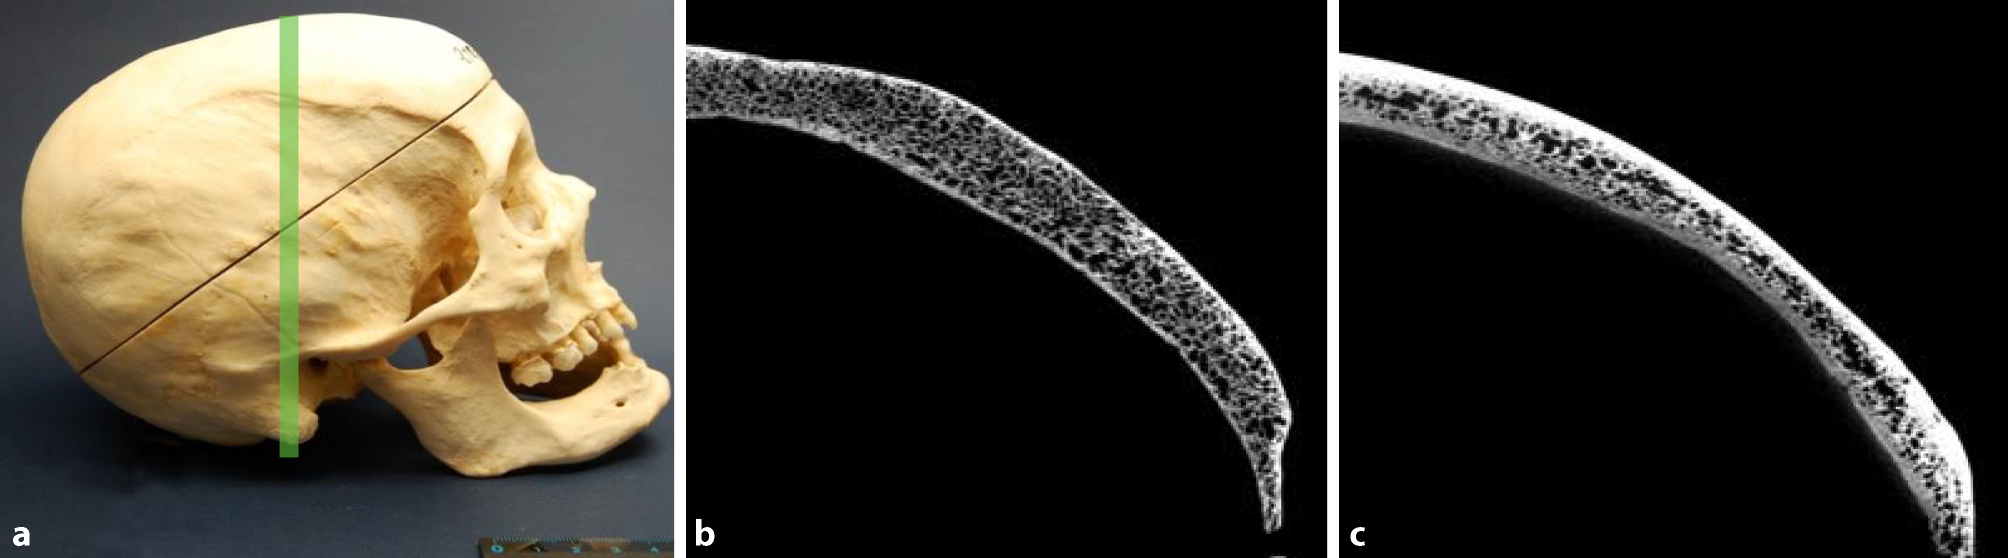

Fig. 2

Sclerotic reorganization. Skull of a 43-year-old man presenting with syphilis compared to a 76-year-old male skull without syphilitic signs used as a control. a Photograph of the skull with macroscopically visible signs of syphilitic alterations. The green line indicates the plane of the scan. b Cross-section of the affected part of the skull obtained by µ‑CT showing lytic destructions and a massive sclerotic reorganization compared to the skull of the 76-year-old man in c lacking any infectious lesions used as control

Sclerotic reorganization was observed in 80% of the syphilitic skull bones. Fig. 2a, b shows a skull of a 43-year-old male showing a massive sclerotic reorganization in comparison to a 76-year-old male control skull (Fig. 2c). The internal and external tables, separated by the diploe, did not show any alterations and are clearly recognizable.